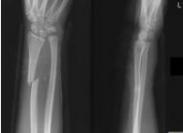

先天性Madelung畸形(馬德隆畸形),是橈骨遠端尺側及掌側骨骺發育障礙引起的先天性遠端橈尺關節半脫位畸形。也有人稱其為先天性腕關節半脫位,橈骨遠端骨骺發育缺陷和尺側部比橈側部短等。

- 常見癥狀:不明原因尺骨莖突異常突起、腕關節向掌側、橈側移位、活動受限、前臂旋轉功能受限、女性多見